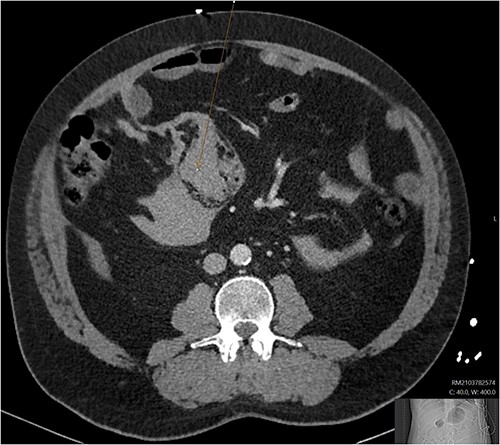

A CT abdomen-pelvis (CT-AP) revealed an acute haematoma inferolateral to the third part of the duodenum and another at the root of the mesentery. High density fluid related to the mesenteric bleed was also seen extending from the right para-colic gutter into the pelvis and in the peri-hepatic region. The patient was admitted under general surgery, stabilized with intra-venous fluid resuscitation, co-amoxiclav and metronidazole and cross matched for four units of blood. A CT-angiogram demonstrated acute haemorrhage throughout the abdomen with a 104 x 62 mm haematoma arising centrally at the level of L2 within the mesenteric fat (Fig. 1). The haematoma did not appear to originate from any specific mesenteric vessels but was related to some mid and distal jejunal loops. The angiogram also showed discontinuity when tracing the proximal and mid jejunal loops inferiorly, extensive haemorrhagic peritoneal fluid around the liver extending inferiorly (Fig. 2) and a small amount of peri-splenic haemorrhagic fluid. Curved reformatting of the angiogram revealed no abnormalities within the superior mesenteric artery (Fig. 3).

Curved reprogramming of the initial CT angiogram. Curved reprogramming of the patient’s initial CT angiogram showed no evidence of an aneurysm within the superior mesenteric artery, effectively ruling this out as a cause of the patient’s acute bleed.